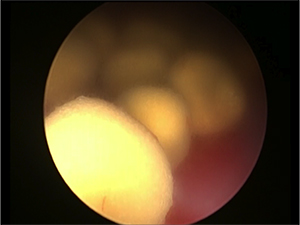

内視鏡カメラにて石の取り残しがないことを確認